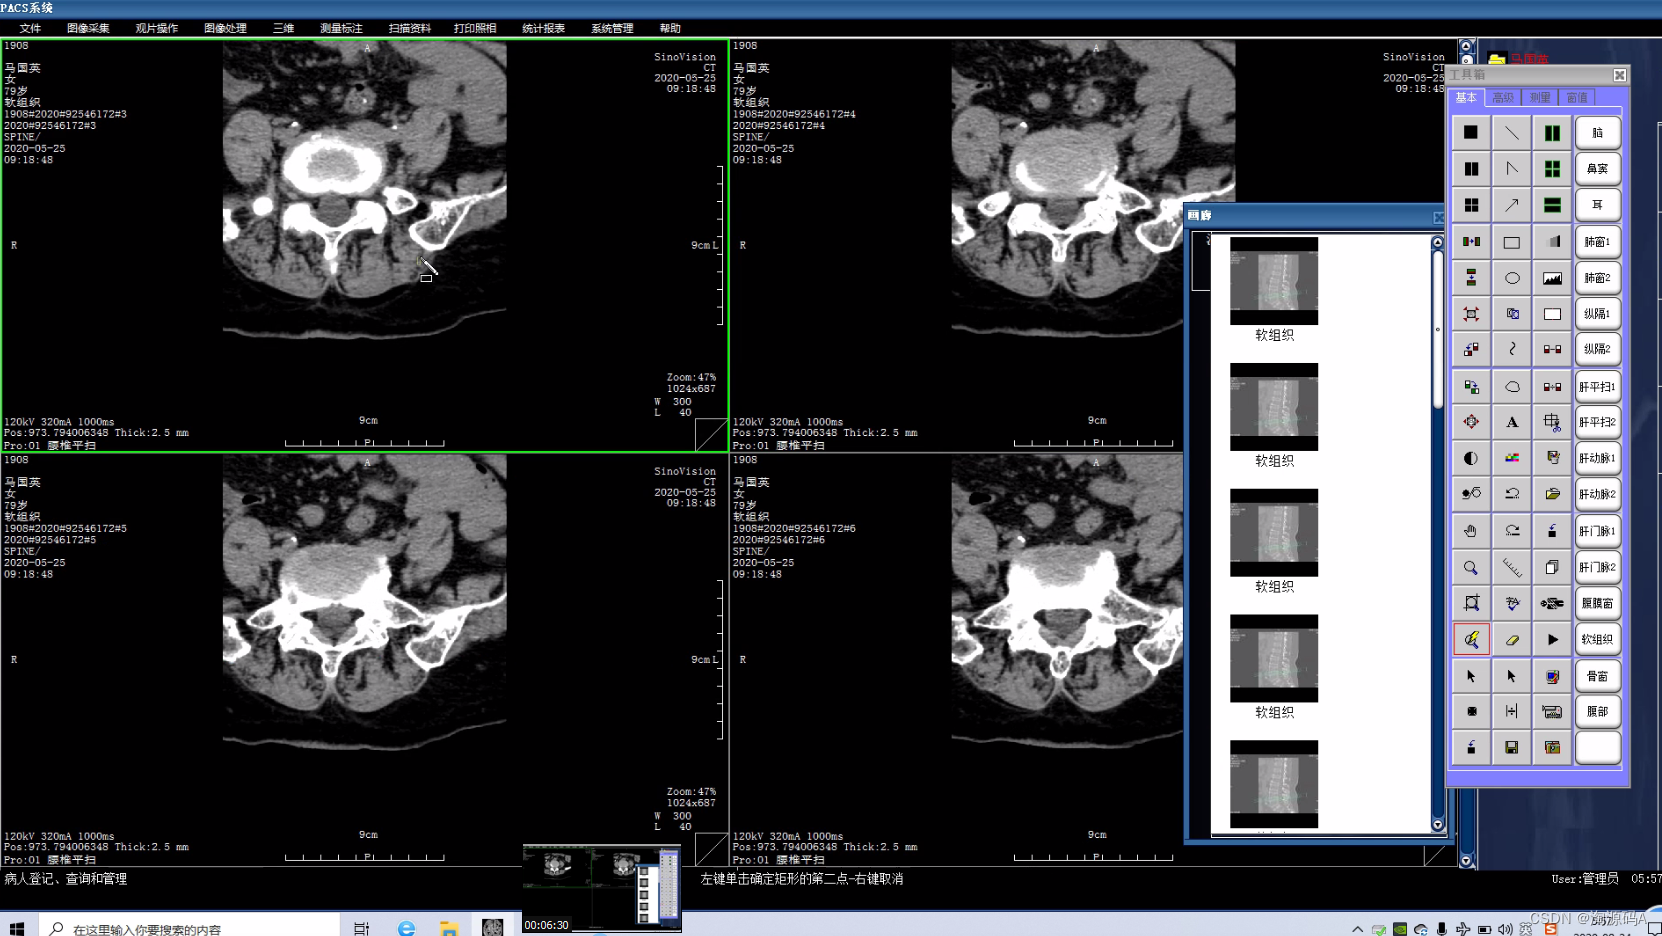

影像处理

图像显示:同屏分格显示病人不同体位、不同设备的图像,供诊断比较检查;显示矩阵任意调节;可自定义显示图像的相关信息,如姓名、年龄、设备型号等参数。

图像处理功能:提供窗宽/窗位调节,负像,图像漫游、缩放、旋转、镜像,动态视频捕捉,伪彩,播放等功能。

测量分析:长度、角度、面积测量,区域密度分析;显示感兴趣区R I分析,R I曲线。

图像标注:直线、箭头、矩形、椭圆、多边形、手画线、文本等格式标注等。

图像增强:图像平滑、边缘增强、对比度调节、降噪滤波、直方图均衡、雕刻效果、锐化等

图像回放:支持数字电影方式回放,播放速度任意调节,单幅、多幅、动态回放已归档的图像。

参数设置:支持用户自定义窗宽窗位值、显示文字的大小、放大镜的放大比例等参数调节。